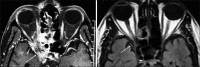

Methods: We conducted a retrospective, interventional study on six consecutive patients with COVID-19 who developed rhino-orbital mucormycosis and were managed at two tertiary ophthalmic referral centers in India between August 1 and December 15, 2020. Diagnosis of mucormycosis was based on clinical features, culture, and histopathology from sinus biopsy. Patients were treated with intravenous liposomal amphotericin B with addition of posaconazole and surgical debridement of necrotic tissue.

Results: All patients were male, mean age 60.5 ± 12 (46.2-73.9) years, type 2 diabetics with mean blood glucose level of 222.5 ± 144.4 (86-404) mg/dL. Except for one patient who was diagnosed with mucormycosis concurrently with COVID-19, all patients received systemic corticosteroids for the treatment of COVID-19. The mean duration between diagnosis of COVID-19 and development of symptoms of mucor was 15.6 ± 9.6 (3-42) days. All patients underwent endoscopic sinus debridement, whereas two patients required orbital exenteration. At the last follow-up, all six patients were alive, on antifungal therapy.